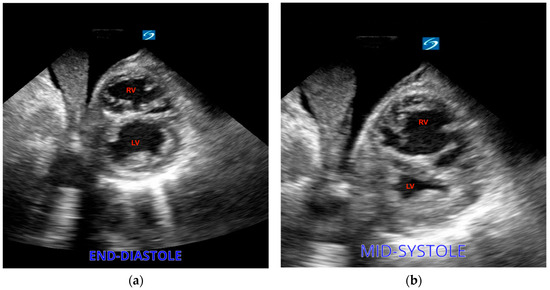

3.4.4. Pulmonary Embolism